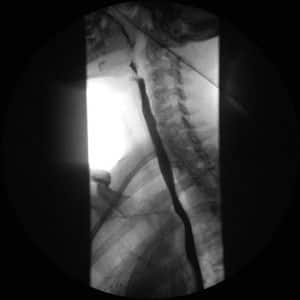

Imagenes obtenidas de un tránsito EGD (esofagogastricoduodenal, secuenciadas a continuación):

Se visualizará el esófago lleno de contraste desde la parte inferior del cuello hasta el cardias y entre la columna vertebral y el corazón en las proyecciones oblicuas y en las laterales. El la proyección PA el esófago se observará superpuesto a las vértebras dorsales